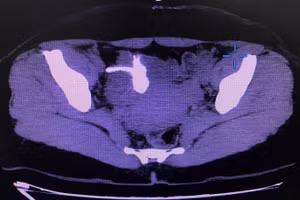

GD&TĐ - Người đàn ông 36 tuổi phải thực hiện cắt bỏ 3m ruột do bệnh xuất huyết tiêu hóa dưới, tăng áp tĩnh mạch cửa, chuyển dạng xoang hang hiếm gặp.